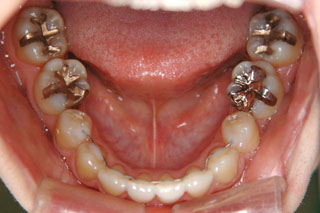

2年半ほどの治療で、装置を撤去し保定治療に移行しています。概ね緊密な臼歯の咬合と前歯の被蓋が確立されました。

保定治療を開始してから2年半が経過していますが、良好な咬合の安定が維持されています。見た目だけではなく、中心位マウントの咬合器にて顎位のズレを計測していますが、計測値は1mm未満の数値である事を確認しています。理想的には中心位=咬合位かも知れませんが、多少の遊びは必ず出てきます。しかしながら最初からルーズなゴールを目指していたら、的を外してしまうでしょう。できれば、ピンポイントで理想を目指したいものです。